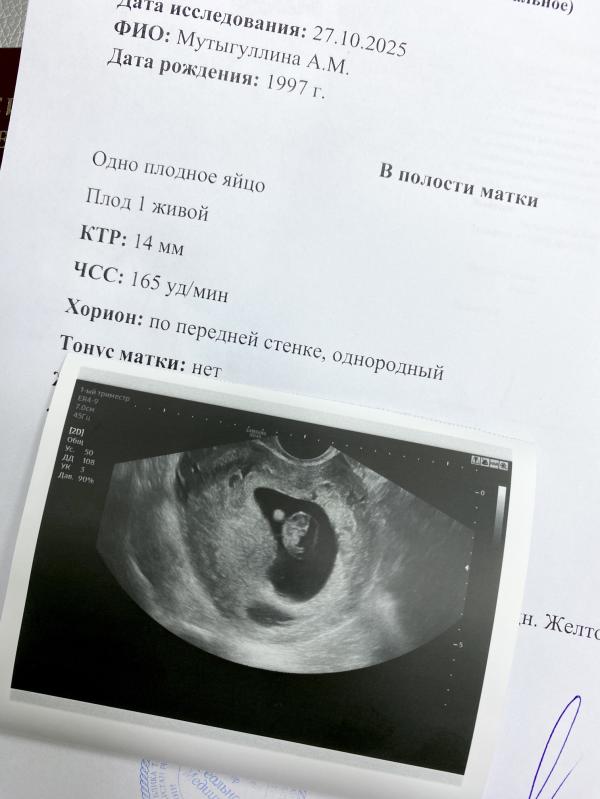

8 недель беременности: переживания перед УЗИ и сердцебиение

Моя маленькая бусинка 🥺❣️

Уже почти 8 недель, сердцебиение найдено, встаем на учет)

Очень переживала перед узи что что-то не так пойдет, начитаешься всякого 🫣